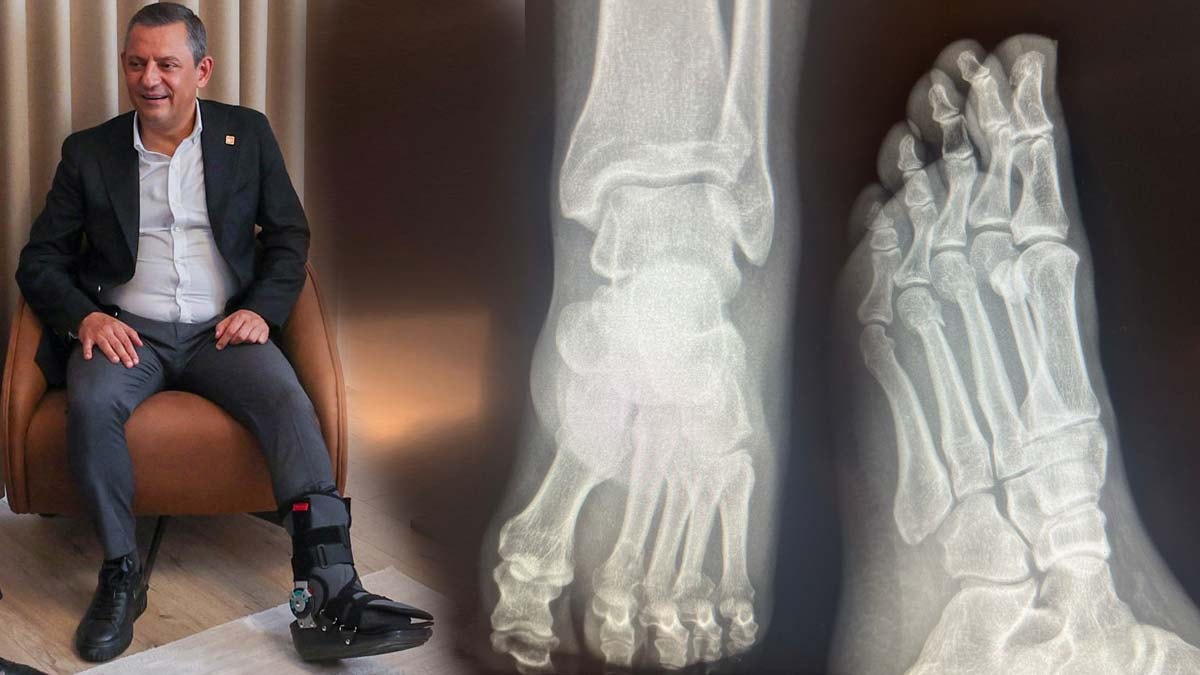

CHP Genel Başkanı Özgür Özel'in geçen hafta evinde geçirdiği kaza sonucunda ayağında kırıklar meydana gelmişti.

Kazanın duyulmasının ardından bazı sosyal medya hesaplarında, Özgür Özel'in ayağından vurulduğu iddia edildi.

Tartışmaların sürmesi üzerine Özel, ayağının röntgen filmlerini paylaştı. (DHA)